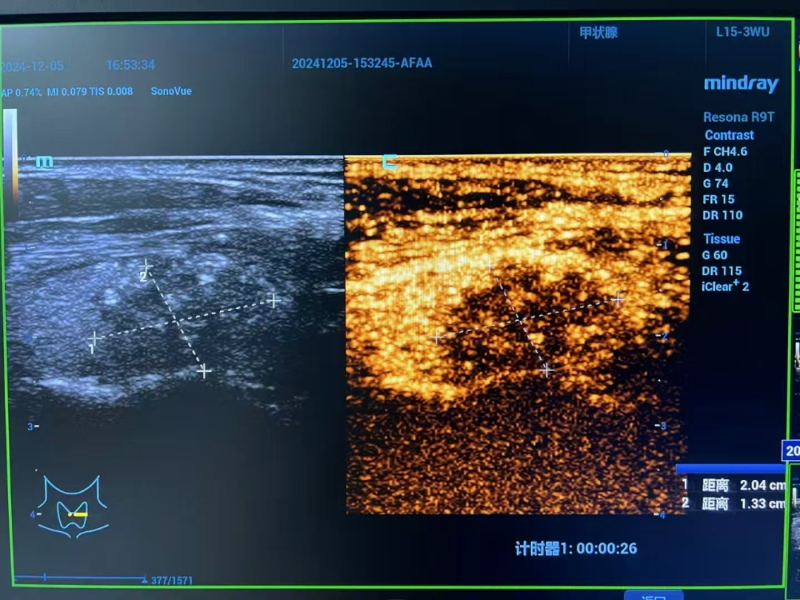

△术后评估

术后超声造影检查喜传捷报:消融区域严密包绕癌灶,癌细胞无处遁形。李女士嗓音清晰如初,颈部痛感几近于无,仅留微小创口,外观几无影响,身心恢复情况良好,术后次日即达出院标准,顺利回归生活正轨。